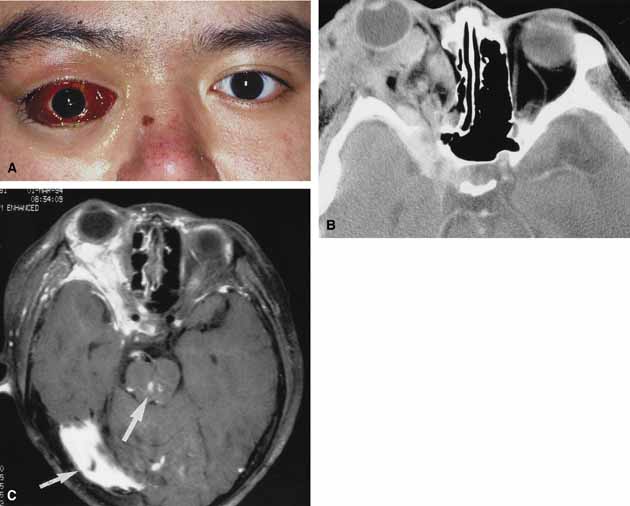

NO-FLOW MALFORMATIONS No-flow malformations (so-called lymphangiomas) have nonfunctional vascular systems that arborize through variable portions of the orbit.73 They may appear as superficial, deep, combined, or complex lesions.74 Clinically they are characterized by syndromes consisting of episodes of acute exacerbation and remission, often related to an upper respiratory tract infection. Although they are hemodynamically isolated from the systemic circulation, nutrient vessels within their fragile walls may be the source of sudden hemorrhage into their lumens, which transforms microscopic channels and cysts into blood-filled macrocysts (so-called chocolate cysts). Hemorrhage within a retrobulbar lesion may be dramatic, causing sudden proptosis (Fig. 8A and 8B). The patient has pain, decreased ocular motility, and decreased vision. Involvement of superficial components will lead to disfigurement of the lid, as well as swelling and ecchymosis of the conjunctiva. Management is similar to other orbital hemorrhages with canthotomy, cantholysis, and/or orbital decompression. Surgical decompression if required is aimed at evacuating the blood-filled cysts. Combined and complex lesions are frequently massive in size involving the intraconal, extraconal, preseptal, and postseptal spaces (Fig. 9A and 9B).75,76 They produce significant cosmetic disfigurement and may extend beyond the confines of the orbit into the intracranial space. In addition, isolated intracranial vascular anomalies may be noted (Fig. 9C). These combined lesions often require orbital surgery either on an acute basis, when there is an acute retrobulbar hemorrhage with optic nerve compression, or on an elective basis to deal with cosmetic disfigurement or chronic compression. Such surgery must be approached cautiously because of the risk of iatrogenic hemorrhage. Oral or intravenous steroids are also beneficial in the treatment of acute flare-ups. VENOUS FLOW MALFORMATIONS Venous flow malformations (so-called varices) generally refer to those vascular malformations with weakened segments of the orbital venous system, of variable length and complexity.76,77 They may appear as superficial, deep, or combined lesions and may be of a distensible or nondistensible variety. Because they are intrinsic to the systemic circulation, distensible primary varices enlarge with increased venous pressure, and their distensibility varies with the residual thickness and strength of their wall. The lesions often cause intermittent proptosis, pain, and/or bruising because of expansion brought about by physical effort (straining, Valsalva maneuver) or bending (Fig. 10A, 10B and 10C).78 Sudden proptosis may result from hemorrhage into one of the varices or the creation of a one-way valve effect trapping blood within the lesion. High-dose steroids, canthotomy, and cantholysis may be of benefit to decrease the orbital pressure. Direct surgical excision is difficult because of the tortuous tangles of fragile, thin-walled malformed vessels and their tendency to rupture and bleed excessively.59 Nondistensible varices may also appear as superficial, deep, or combined lesions. Clinically they are similar to lymphangiomas and characterized by episodes of acute exacerbation and remission related to hemorrhage or thrombosis within the lesion. Hemorrhage into deeper lesions causes sudden proptosis, pain, decreased motility, and reduced vision. Profound orbital hemorrhage with visual deterioration and pain is treated in a manner similar to that of lymphangioma and orbital hemorrhage (canthotomy, cantholysis, and/or orbital exploration with evacuation of clotted blood and excision of the associated lesion). ARTERIAL FLOW MALFORMATIONS Arterial flow malformations are distinguished by evidence of arterial flow. The primary examples are arteriovenous malformations that have a direct flow from the arterial side, through a malformation, and then to the venous side of the circulation. Arteriovenous malformations are characterized by high arterial flow directly into the anomaly that exits through the normal venous channels, which may arterialize. Thus, they bypass the orbital system and more commonly act to shunt blood away from rather than into normal vascular channels.59 Clinically they are associated with pulsating exophthalmos or recurrent episodes of hemorrhage or thrombosis (Fig. 11A and 11B). They are often associated with a bruit (which may be heard by the patient) and may cause pain when engorged with straining or Valsalva maneuver. With imaging, orbital arteriovenous malformations are characterized by irregular, rapidly enhancing masses that may have high flow characteristics on Doppler studies and flow voids on MRI scanning (Fig. 11C, 11D, and 11E). Direct selective angiography will demonstrate the engorged, rapidly filling proximal arterial system, the malformation and the distal venous outflow. Management may involve selective gluing followed by excision. For those lesions with feeding vessels that are outside the orbit, a direct cut-down followed by embolization and surgery is also a safe and direct approach.59 |